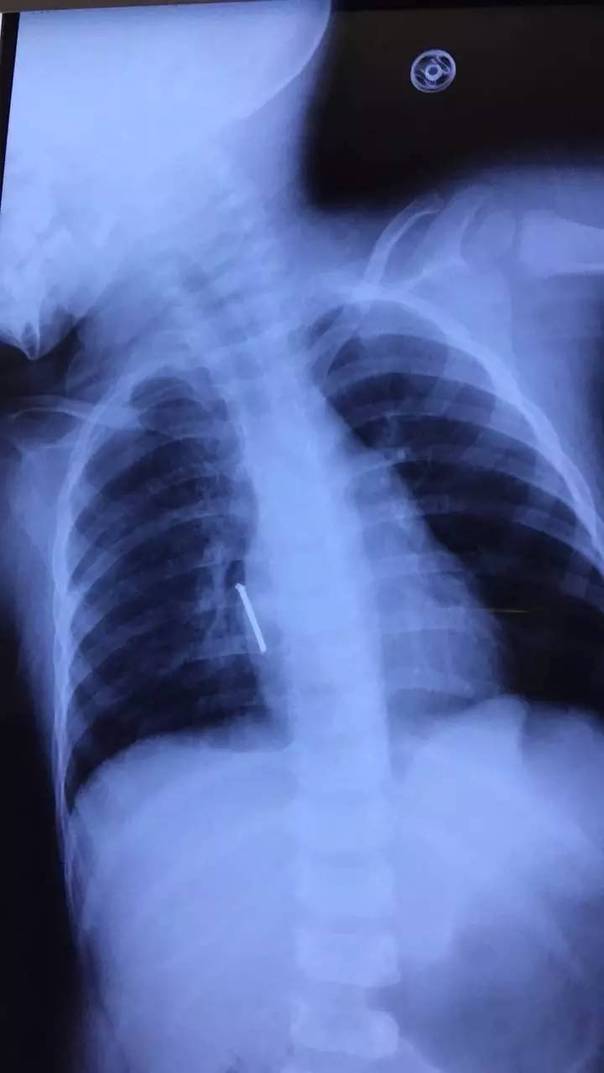

钉子在随着心脏的跳动起伏

钉子尖就靠近心脏

一瞬间,一把长5公分左右的钉子射进阳阳的心脏附近!据了解,气钉枪打出钉的力度很大,很有冲击力和杀伤力,速度一般60米/秒,厉害的可射穿1cm钢板!许先生看到此景,整个人都蒙了!带阳阳火速去医院,心里不停祈祷:“千万别刺到心脏!千万别……”

从片子上看,钉子尖就靠近心脏

“从片子上看,钉子尖就靠近心脏!如果直接拔钉子,钉子穿透心脏的话,会引起大出血,继而危及生命,也可能胸腔内存有大量积血会填塞心脏,十分危险。”

在进行充分评估后,专家们决定手术打开胸腔,后发现钉子的钉尖已经穿入右心房肌层3毫米,造成胸腔积血150毫升!“如果钉子再深入一点,那抢救都来不及了。”所幸手术顺利,阳阳脱离了生命危险。